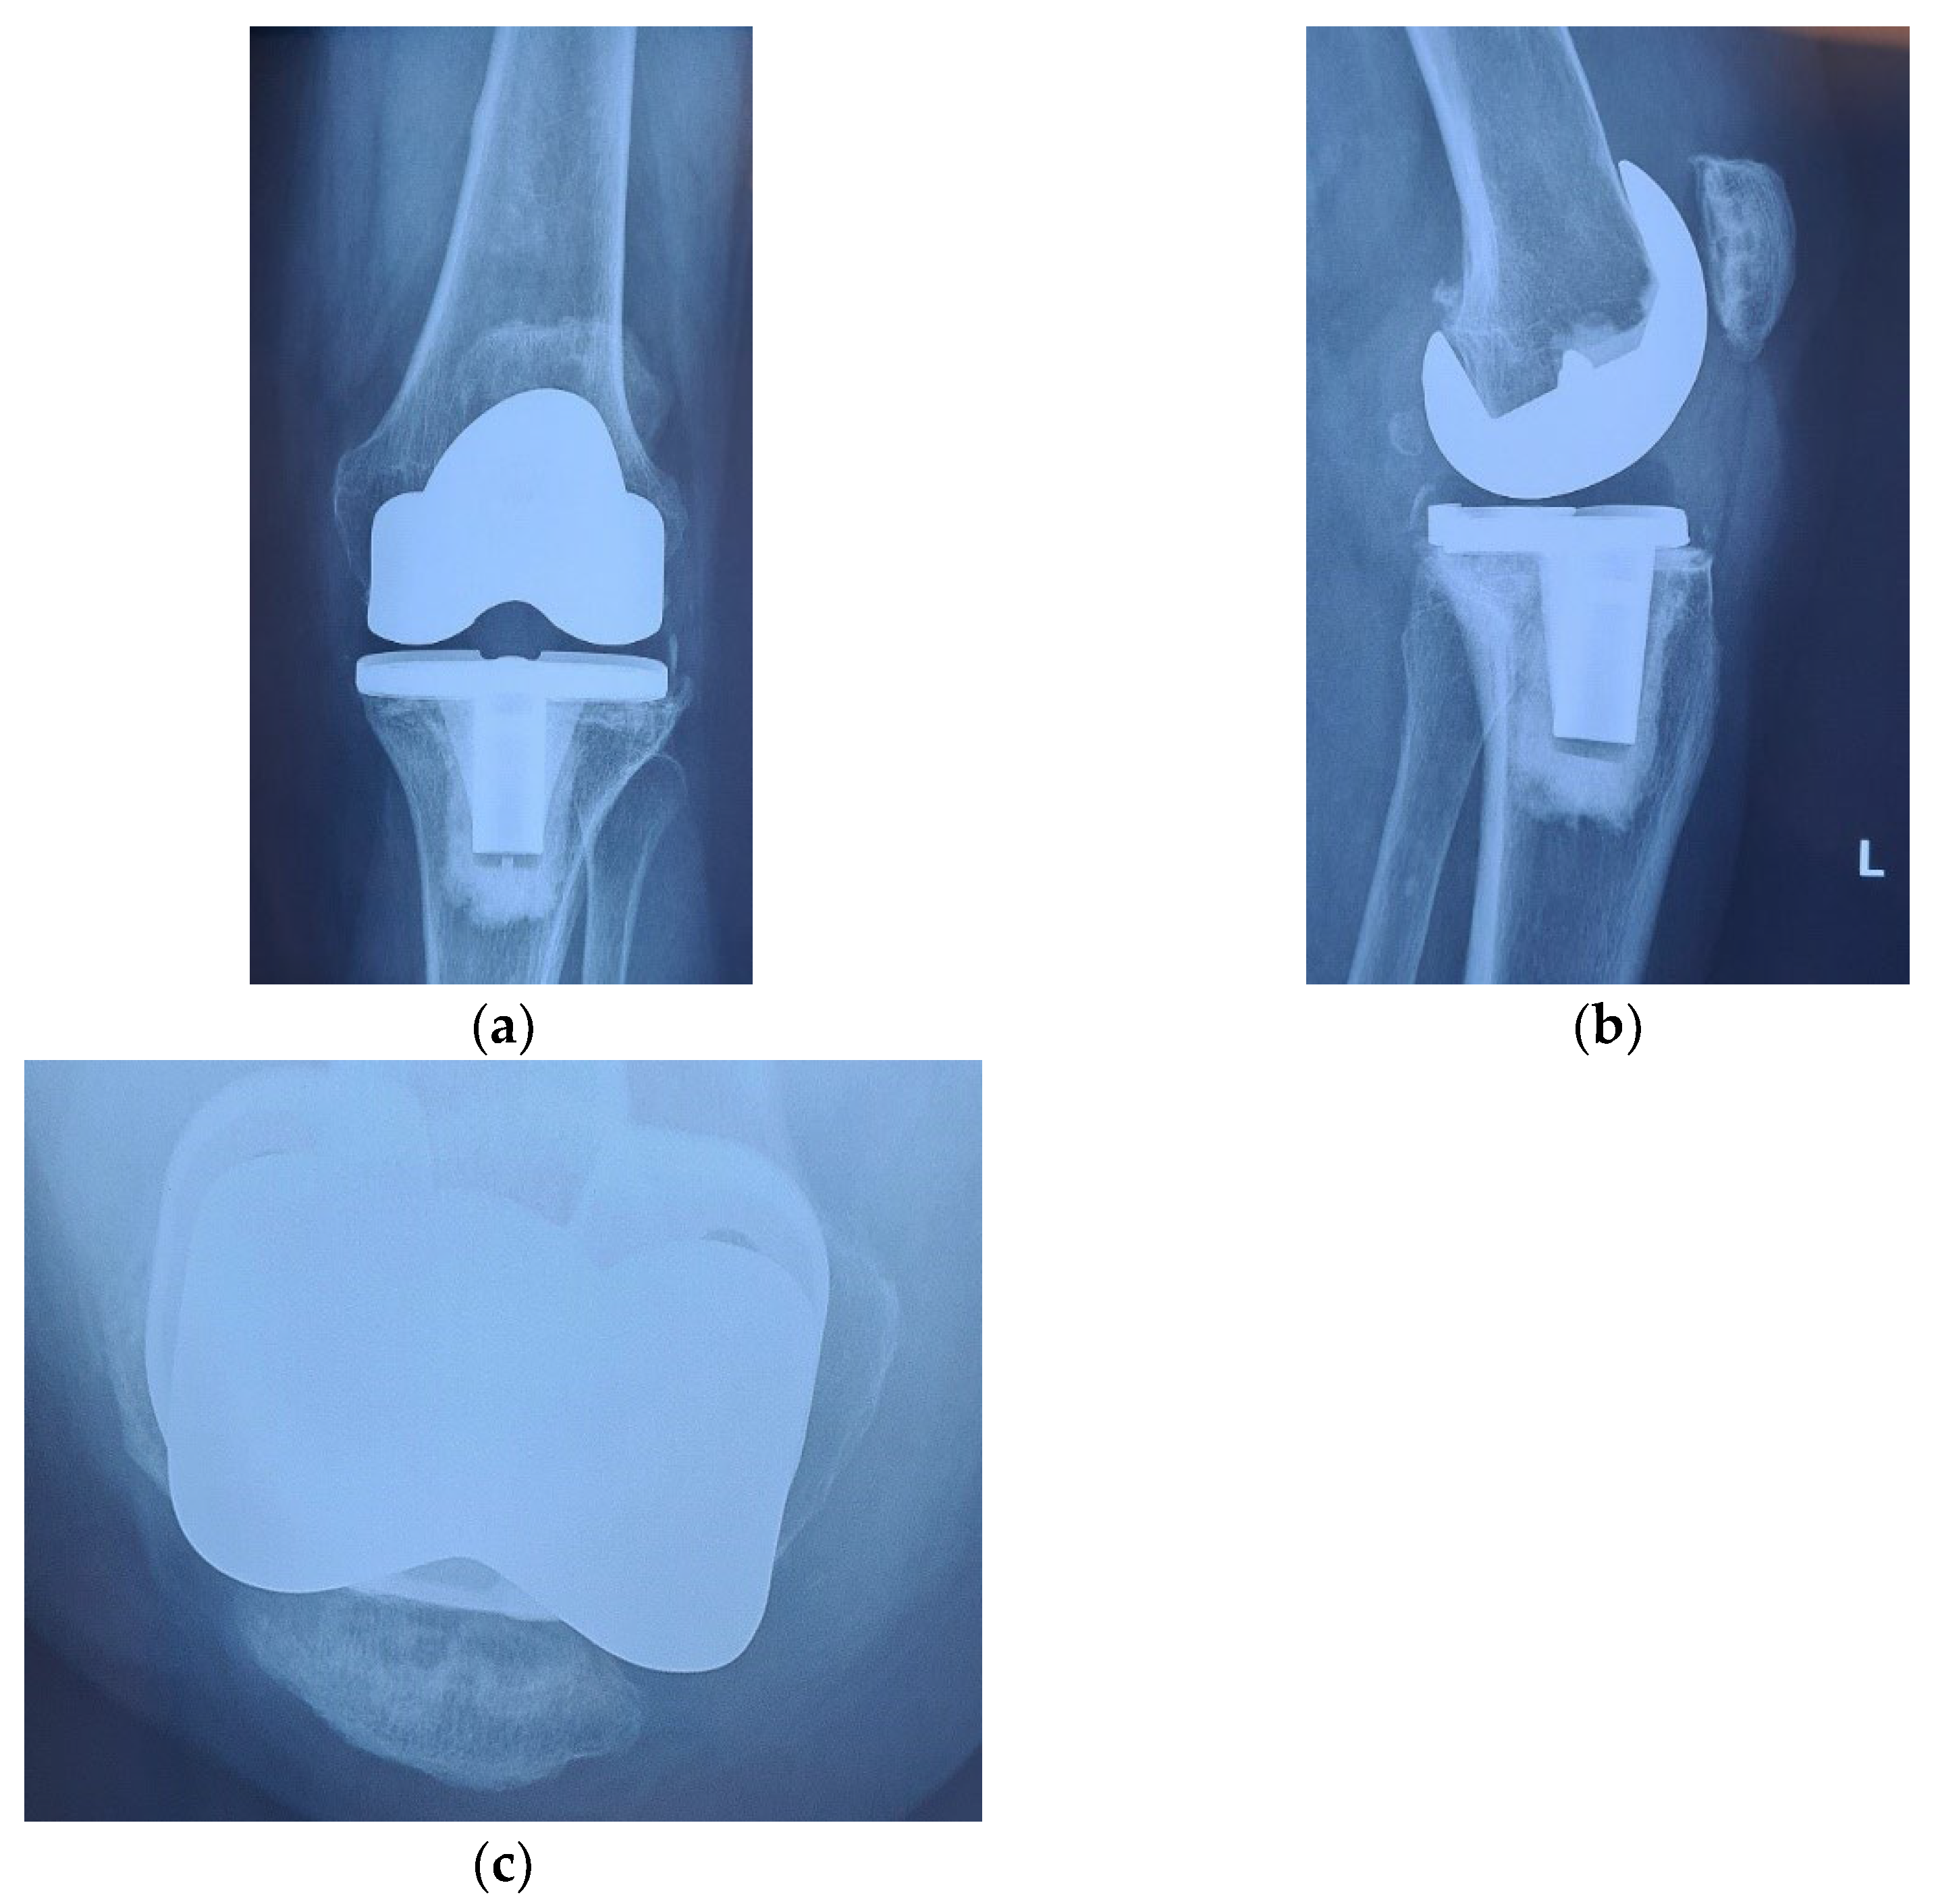

Alongside with the clinical scores, the patient was also evaluated radiologically, with CT scans and standard X-rays. Radiological investigations, using coronal, lateral and axial views (Merchant view) showed patellar arthrosis and a slight lateral subluxation of the patella (Figure 4).

Figure 4.

(a) coronal view, patellar lateral subluxation (arrow) compared to femoral axis with (1) marking the femoral trochlear axis, (2) patellar axis and (3) the patella must be centered in the femoral trochlea; (b) lateral view, patellar wear, patellar trochlea deformation and subchondral bone condensation with (4) marking subchondral osteocondensation and (5) patella bone deformation; (c) axial view, patellar lateral subluxation, and deformation, osteocondesation of the subchondral bone with (6) patella bone deformation and condensation, (7) femoral trochlear axis and (8) Patellar axis.

CT images, subject to artifacts generated by the implant, show patellar wear and peripatellar inflammatory phenomena (Figure 5).

Figure 5.

CT images: (a) Sagittal view showing patellar arthrosis, condensation of subchondral bone. (b) Axial view showing patellar arthrosis, deformation, and lateral subluxation (arrow) with (1) marking the femoral trochlear axis and (2) patellar axis; (c,d) CT 3D image, peripatellar inflammation.